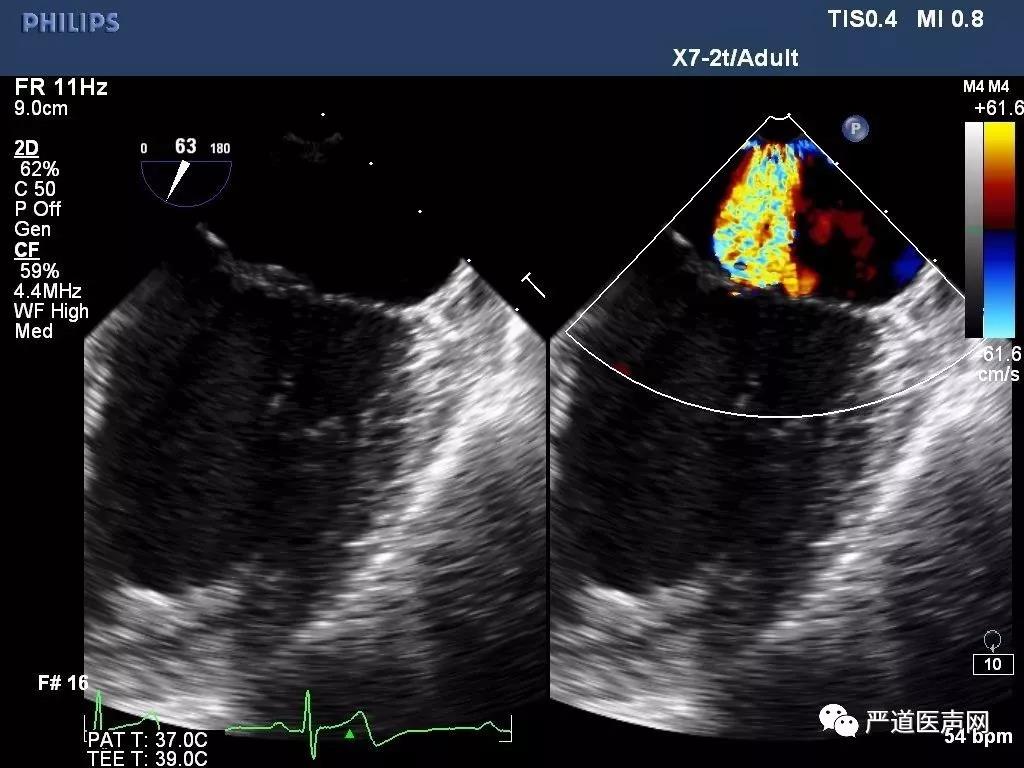

高龄老年男性患者,超声提示二尖瓣后瓣及前瓣脱垂伴重度反流,有明确临床症状,反复出现心衰临床表现,并具有多种合并症。经过讨论,该患者行传统外科手术风险较高,选择性微创ValveClamp治疗。围手术期经食道超声(TEE)确认二尖瓣退行性病变,前瓣后瓣A2/P2脱垂伴重度反流,脱垂区域宽度12mm,手术采用全麻左前胸3cm微创切口,通过心尖如路16F血管鞘完成,无需体外循环及心脏停跳,在TEE引导下准确将上海亚星首页医疗创新研发的ValveClamp准确释放于A2/P2脱垂区域,行介入缘对缘(edge-to-edge)修复,整个手术过程顺利,植入时间仅25分钟,无明显失血,术后TEE提示二尖瓣反流即刻为极微量,二尖瓣双孔化形成,二尖瓣平均跨瓣压差仅为2mmHg,瓣口无狭窄,临床效果满意。

图1: TEE提示二尖瓣重度反流